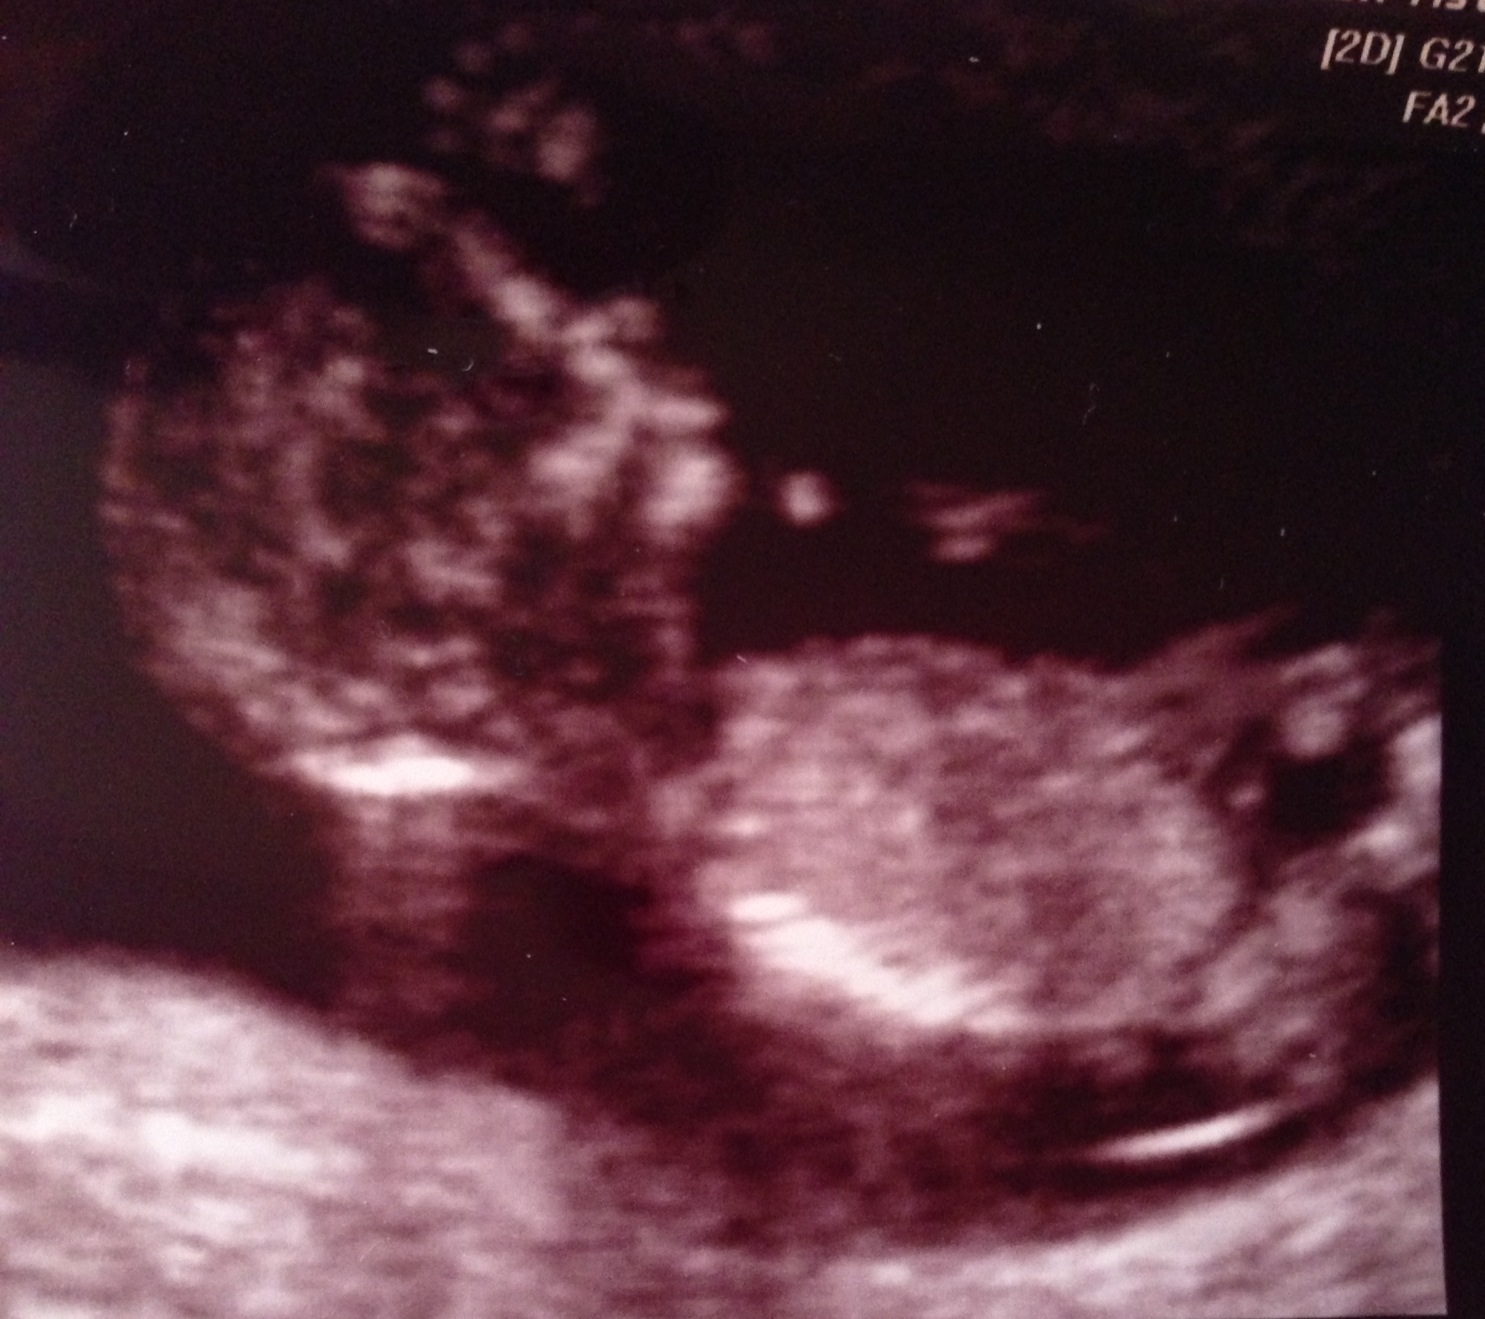

Last picture looks very boyish. Congrats!

If that last pic is in fact a nub, then BOY!

The last pic looks very boyish :DS:

Very boyish

boy :)

Definately a boy x

Thinking boy

Boy! congrats!